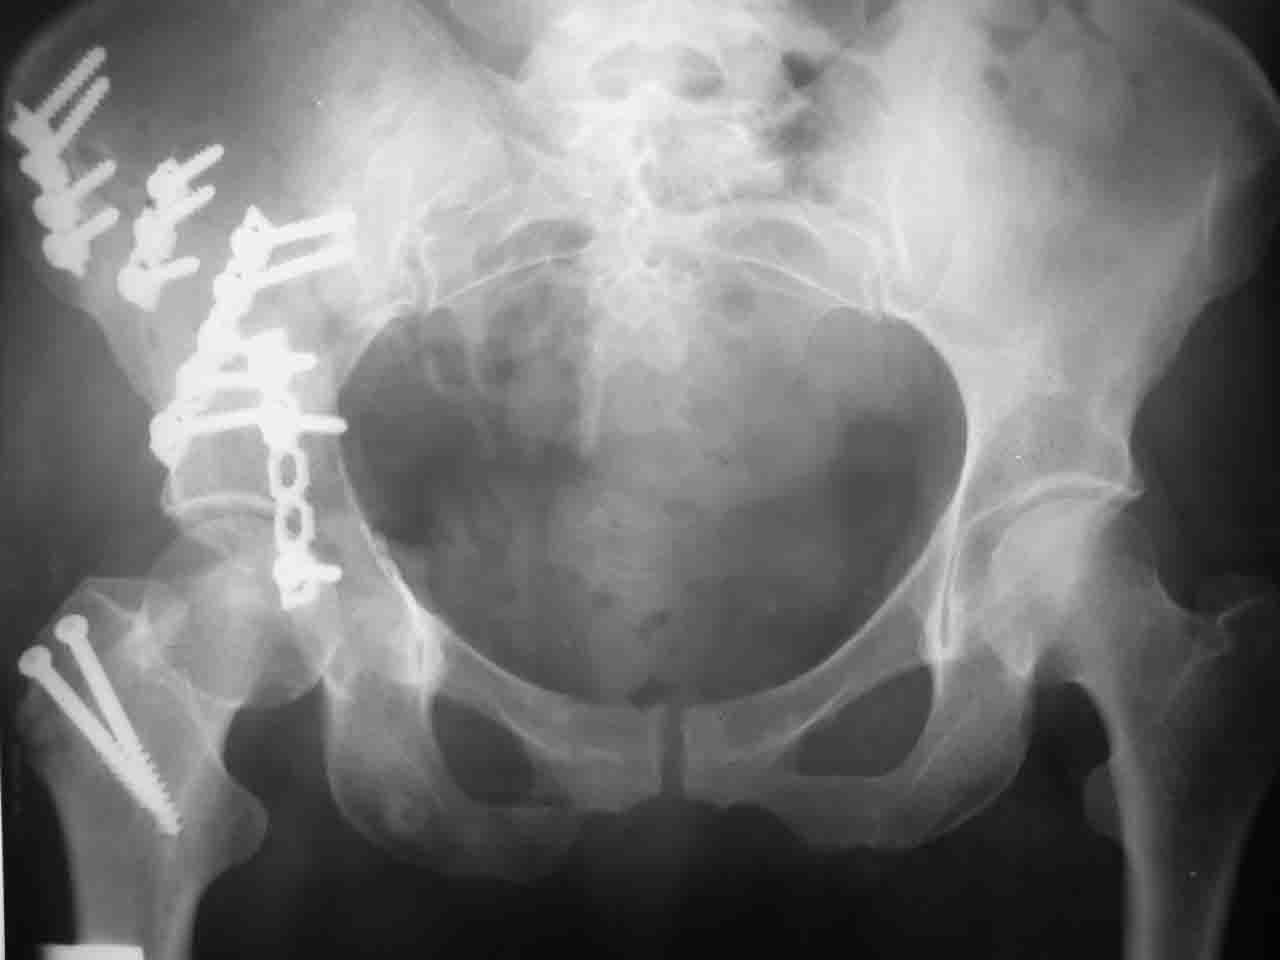

А какой отдел вертлужной впадины более важен передний или задний? Чем был обусловлен выбор доступа к суставу? Проще говоря, почему вы пошли передним доступом на двухколонный перелом? Мне понятны ваши сомнения, когда не удется сделать все что хотелось бы. В данном случае доступ должен быть чрезвертельным боковым (как и советовал Рунков) или двумя доступами.

> передним доступом на двухколонный перелом?

Илеофеморальный доступ не совсем передний и сравнительно с илеоингвинальным, и Кохера-Лангенбека открывает весь наружный таз кроме самых передних отделов лонных костей, фиксацию которых я не ставил в задачу. Обширность диссекции, большая длительность операции и более высокий риск гетерооссификации - отрицательные моменты в обмен на возможность легче ориентироваться.

Вопрос доступа к вертлужной впадине при остеосинтезе задача не простая. Конечно, у Летурнеля и Тайла всё давно описано, нам остается только брать на вооружение. Но сами понимаете, что не бывает двух одинаковых ситуаций, поэтому в каждом случае вопрос решается сугубо индивидуально. Наша главная цель - восстановить анатомию с нанесением минимальной дополнительной травмы тазобедреннному суставу, думаю с этим никто не поспорит. Расширенный илиофеморальный доступ уж слишком травматичен (как сказал один коллега "таз лежит отдельно, больной отдельно").Стоит ли делать из пациента анатомический препарат для того чтобы легче ориентироваться. Да и нужно ли собирать всю "мозаику"? Мы применяли при таких операциях своеобразную операционную хитрость - сначала устраняли грубое смещение крыла под гребнем с фиксацией так называемой "плавающей" пластиной (временно фиксированной на двух винтах)- доступ или продлевали боковой, или делали небольшой дополнительный разрез над гребнем. Это позволяло устранить грубое смещение и захождение отломков тела повздошной кости, что значительно облегчало репозицию и остеосинтез впадины над сводом. Основное внимание конечно же уделяли нагружаемому задне-верхнему отделу. Сообщите ваш адрес, пришлю схемы и рентгенограммы.